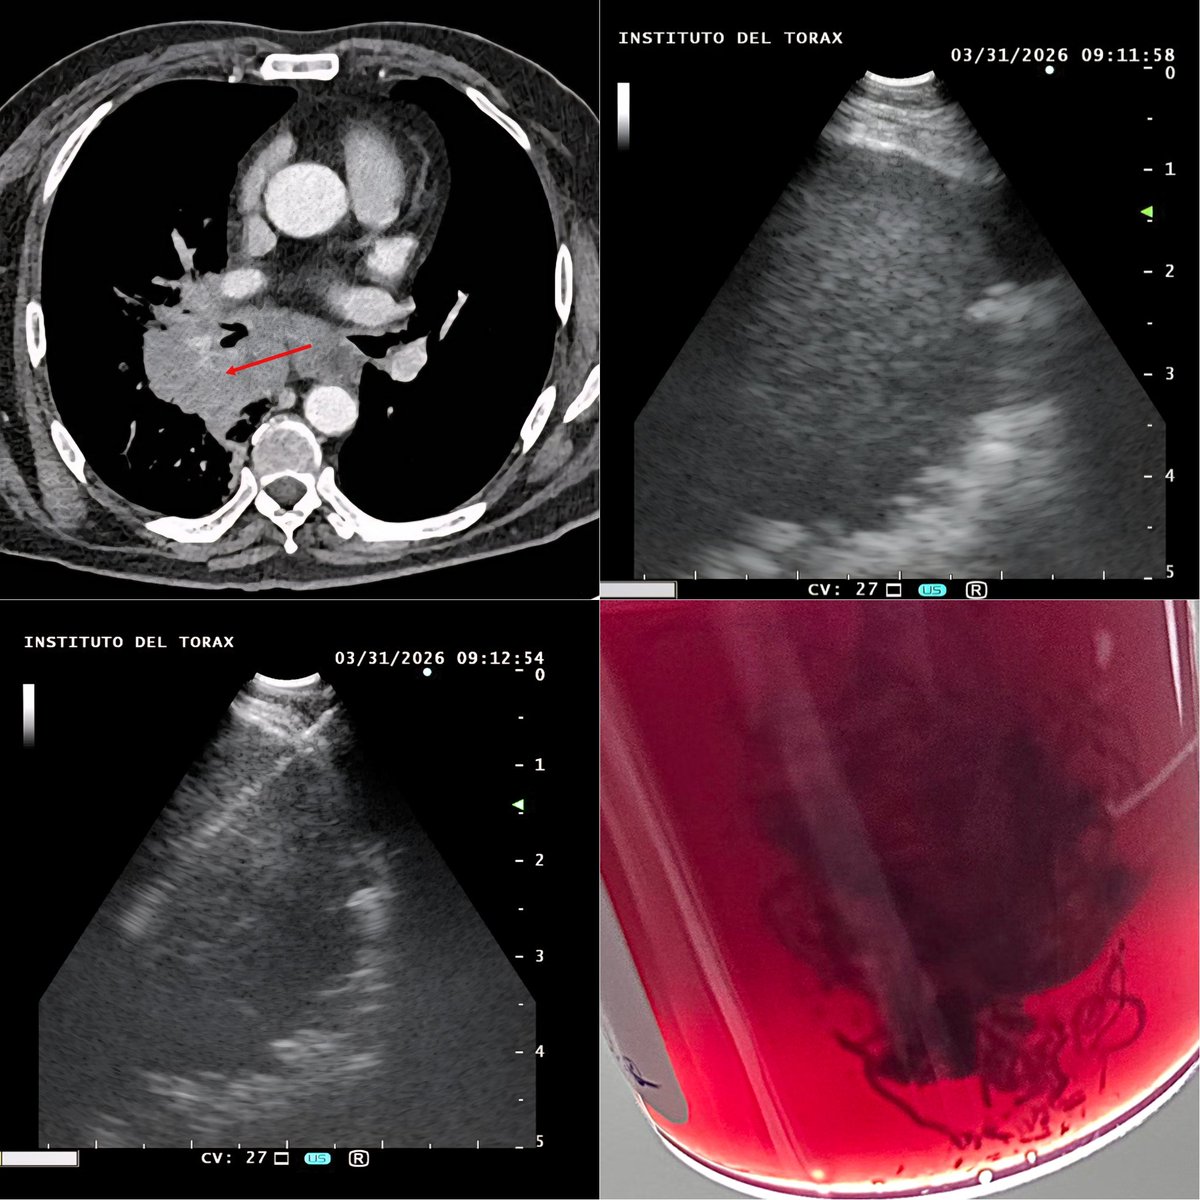

Encabezados por la Dra. Begoña Yarza y la Dra. Cecilia Muñoz, coordinamos con centros de todo Chile la Red Nacional de Derivación hacia el @Toraxchile, para optimizar la atención en intervenciones cardíacas de alta complejidad.